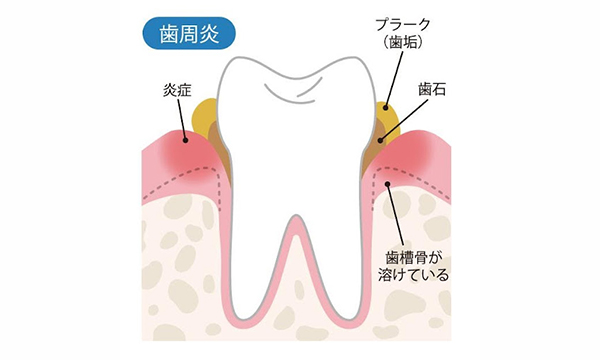

歯槽膿漏とは

歯槽膿漏は、歯科用語では歯周炎といい、細菌によるダメージが歯ぐきだけに留まらず、歯を支える骨にまで達している状態を指します。

プラーク1mgのなかには、およそ300種類1億個の細菌が存在しており、歯ぐきに付着することで炎症を引き起こします。これが歯肉炎の始まりです。

つまり、お口の中に細菌が多い状態が続くと歯肉炎、歯周病の原因になります。